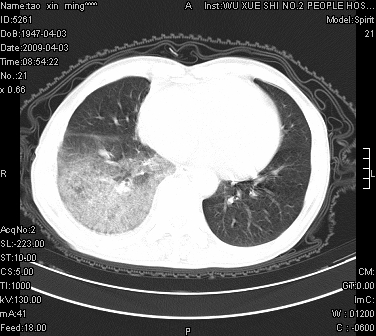

男.62.咯血.胸痛

是不是外伤的,看起来右侧肋骨骨折,右肺唑伤,右胸腔积血, 右肺背段可见一软组织肿块,边缘清晰,可以和中中央型肺ca合并

肺出血,周围型肺癌,右侧胸腔积液

明天请武大中南医院外科熊主任手术.患者无外伤.我考虑肺癌

右下周围型肺癌,右侧胸腔积。

右下周围型肺癌,右下肺出血,右侧胸腔积。

1)考虑右肺下叶周围型肺癌,并右肺下叶肺出血。2)右侧少量胸腔积液。

1)考虑右肺下叶周围型肺癌。2)右侧少量胸腔积液。

右下肺阴影,右胸腔少量积液。